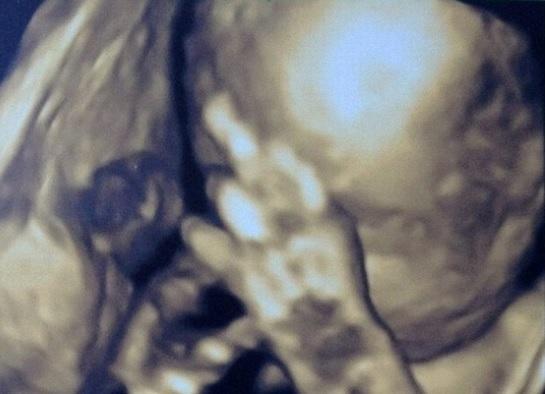

Cu siguranţă acest bebeluş va deveni vedetă, pentru că încă din pântecele mamei se comporta ca atare, atunci când simte că este "urmărit de paparazzi".

Imaginea a fost publicată de Daily Mail şi imediat a fost răspândită şi pe reţelele de socializare, utilizatorii gustând din plin gluma.

Mămica a povestit jurnaliştilor că medicii încercau să îi mute mâna pentru a-i vedea mai bine faţa, în timpul ecografiei. Vizibil deranjat, fătul le-a arătat degetul mijlociu, apoi şi-a încrucişat mâinile, ca un om supărat.

"Cred că bebeluşul va deveni cu siguranţă un star rock", a glumit viitoarea mămică.